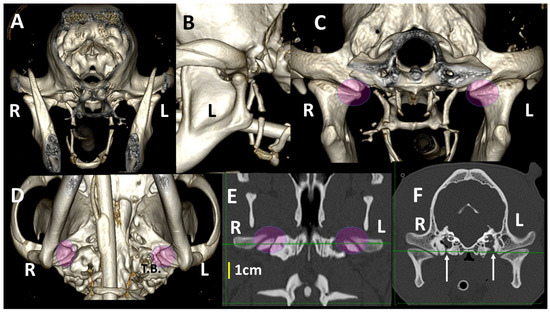

3.3. A Detailed Assessment of Each TMJ Comparing 3DVR Images with the Three Standard CT Planes

3.4. A Pictorial Essay of 3DVR Images in Some Pathological Cases